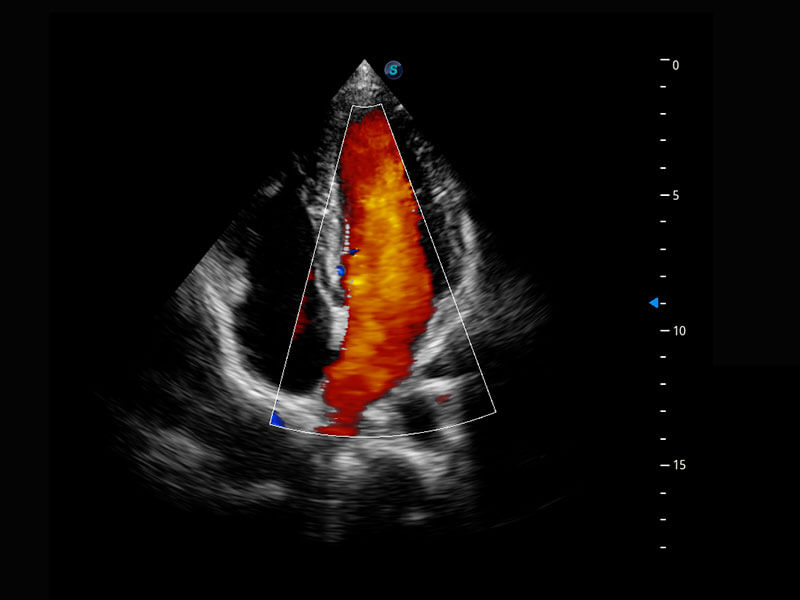

P60搭载一系列胎儿心脏成像技术,实现精细的胎儿心脏评估。

四腔切面

四腔心血流

右室双出口

胎心容积成像